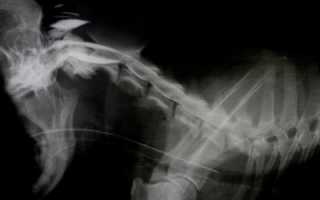

Рентгеновские снимки требуются для исключения возможных механических повреждений позвоночного столба, рентгеноконтрастных новообразований, деформаций позвонков. По рентгенограмме оцениваются межпозвонковые промежутки (если диск минерализован, его можно заметить в межпозвонковом пространстве или в позвоночном канале), форму позвонков, их положение относительно друг друга.

Миелография — это исследование, которое проводится для уточнения диагноза, более конкретного определения локализации патологии. Для проведения данного диагностического мероприятия специальное контрастное вещество вводят под арахноидальную оболочку спинного мозга и проводят рентгенографическое исследование. Контраст очерчивает контуры спинного мозга и нервные корешки, тем самым делает видимыми структуры, невизуализируемые на обычном рентгеновском снимке.

Миелография собаки с межпозвоночной грыжей С2-С3

Межпозвоночная грыжа между 3-4-м шейными позвонками.

Миелография Собаки с межпозвоночными грыжами Th13-L1, L1-L2, L2-L3.

Множественные межпозвоночные грыжи в поясничном отделе у немецкой овчарки.